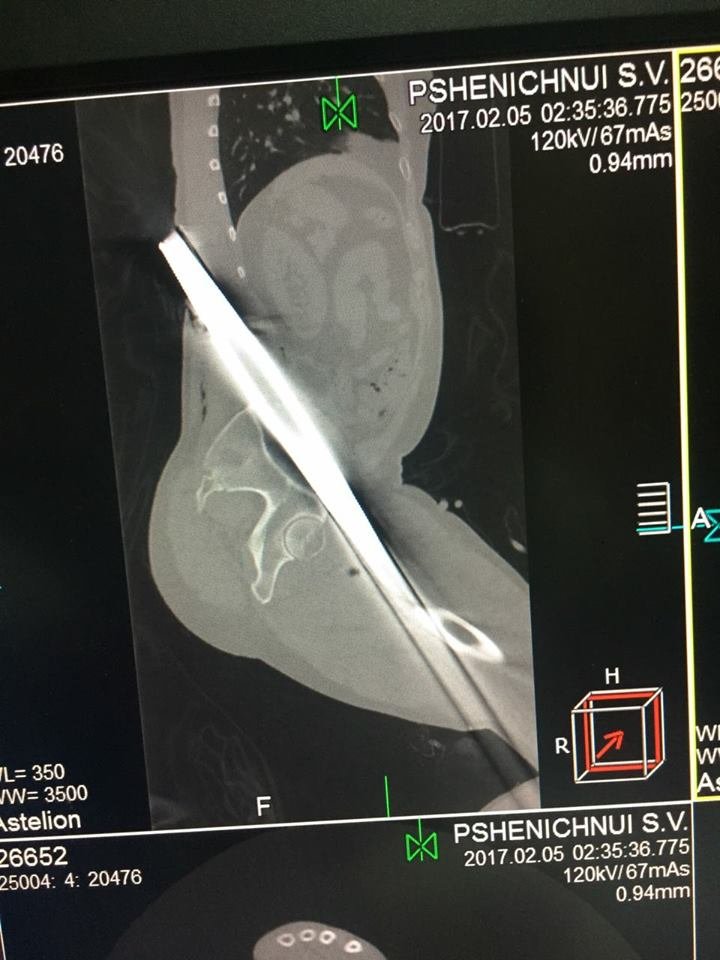

Заведующий приемно-диагностического отделения больницы имени Мечникова Петр Давыденко рассказал, что металлический профиль буквально насквозь проткнул мужчину.

"Итог: инородное тело левой голени, левого бедра, левой половины таза, левой половины поясничной области, открытый многооскольчатый перелом верхней трети левой большеберцовой кости, травматический шок", - отметил врач.

Первую медицинскую помощь пострадавшему оказали в Царичанке, после чего мужчину доставили в Мечникова. Осмотр немедленно провели дежурные травматологи, урологи, хирурги и нейрохирурги. Провели операцию по удалению инородного тела, ПХО ран, лапароцентез, а также объемное переливание препаратов крови.